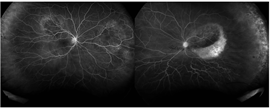

The patient presented with new worsening vision in both eyes. Around one month prior to presentation, he was switched to immunotherapy with ipilimumab, nivolumab, and cabozantinib. Visual acuity measured count fingers in both eyes from a previous 20/80 in the right eye (OD) and 20/200 in the left eye (OS). Intraocular pressure, pupillary exam, and confrontational visual fields were normal. Anterior segment examination was overall unremarkable with clear corneas and trace nuclear sclerotic cataracts bilaterally. Dilated fundoscopic exam showed new mild bilateral vitritis and stable bilateral choroidal lesions with overlying pigmentary changes (Figure 1). Greater subretinal fluid was present in the macula than previously observed. Optical coherence tomography confirmed increased subretinal fluid and revealed a subretinal fibrinoid response (Figure 2).

Figure 1. Color fundus photos showing bilateral choroidal lesions with overlying pigment changes. |

Figure 2. Spectral-domain optical coherence tomography (SD-OCT) demonstrating intraretinal fluid, and subretinal fluid with subretinal fibrinoid response bilaterally. |